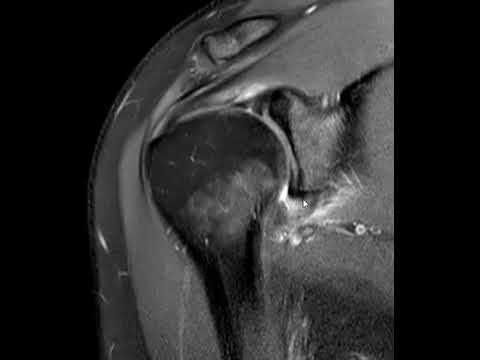

• Magnetic Resonance Imaging (MRI): This is where things get really interesting. MRIs provide detailed images of both bone and soft tissue. They can reveal thickening of the joint capsule—a clear indicator of adhesive capsulitis.

• MR Arthrogram: This involves injecting contrast dye into the joint before the MRI. It highlights issues even better! You essentially get a clearer view of how the capsule is behaving.

• MRI: This method is great for visualizing soft tissues. It helps in assessing the shoulder capsule and surrounding structures. It can show inflammation or thickening of the capsule quite clearly.

Here’s the thing: in adhesive capsulitis, what happens is that the capsule around your shoulder joint becomes thickened and inflamed. But on an X-ray? It can look pretty normal! That’s why doctors sometimes turn to MRI scans. MRIs show soft tissue really well and can reveal changes in the capsule itself that are characteristic of frozen shoulder.